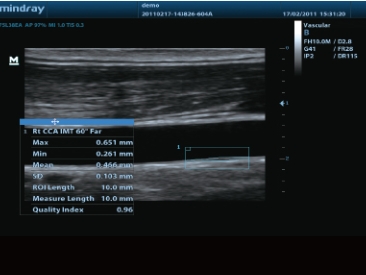

IMT血管内中膜测量